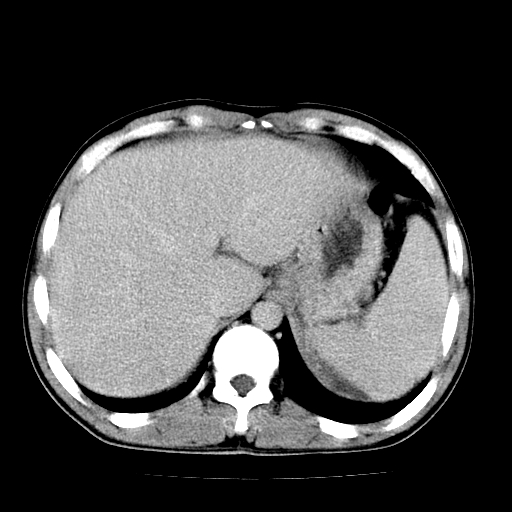

以下是引用天南地北在2007-4-30 13:36:00的发言:[br]支持慢性胰腺炎伴有假性囊肿

以下是引用andymaomao在2007-4-30 14:28:00的发言:[br]支持:1.慢性胰腺炎并假性囊肿形成可能;[br] 2.左肾形态稍增大,旋转不良。